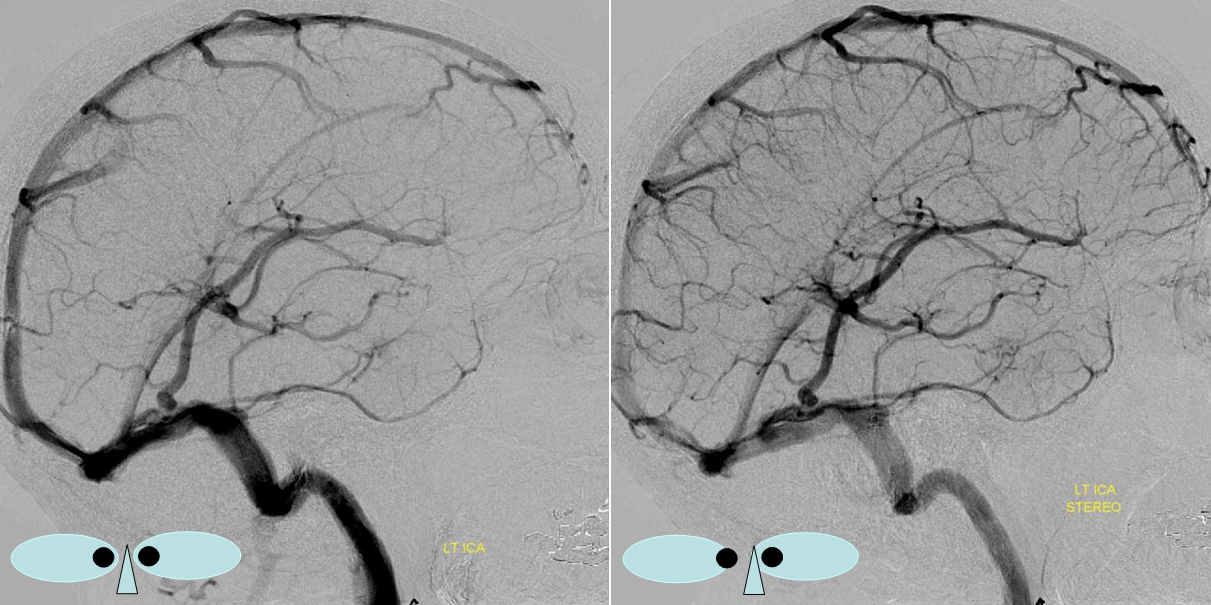

The general neurosurgical fact that the anterior third of the superior sagittal sinus can be safely sacrificed is true almost all the time. When it is not, consequences can be catastrophic. Normally, few veins drain into the anterior 3rd of the SSS, and these usually have collaterals. However, occasionally a large frontal or sylvian vein happens to drain anteriorly. Taking this sinus means risking a venous infarct. Here is an extreme example of dominant inferior left frontal vein draining into the anterior third of the frontal sinus, on MRI. Case courtesy Dr. Howard Riina

Angio is much easier to appreciate. It is well to learn how to spot these veins on MR or CT, as most patients don’t get presurgical angiography for nonvascular lesion